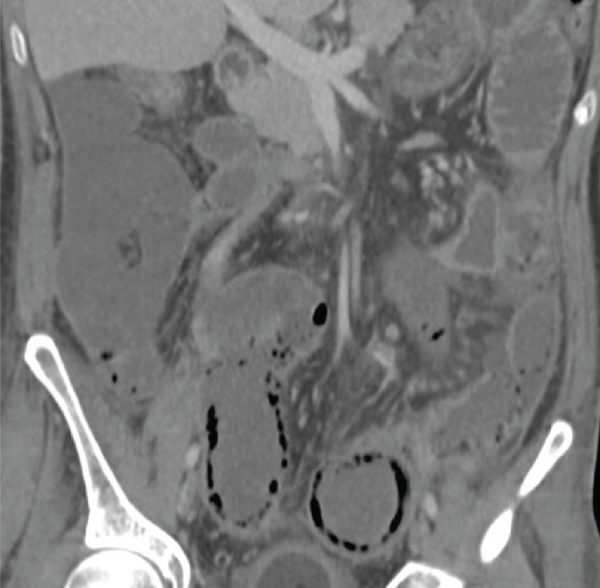

Imaging findings of pneumatosis intestinalis posttransplant are unique as compared to PI seen in other scenarios such as bowel ischemia. PI in posttransplant patients has a bubble-like/expansile appearance with a significant amount of air within the bowel wall (Figures 1 and 2). In these patients, it is helpful to view the pneumatosis on lung windows in order to properly assess its extent (Figure 3). In contrast, for PI in a patient with intestinal ischemia (Figure 4), imaging findings show more of a thin rim of gas bubbles within the submucosa without the expansile appearance. Although posttransplant PI can appear as a thin layer of gas, it would be unusual for intestinal ischemia to appear as bubble-like/expansile. Thus, if the bubble-like/expansive appearance of PI is seen, it may support a benign etiology and clinical course.

(a)

(b)